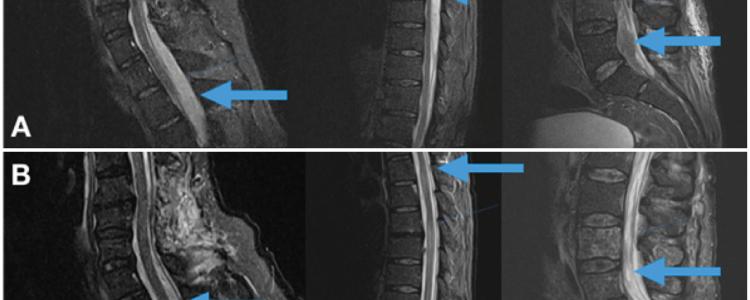

El empiema epidural espinal (EEE) multinivel es una infección rara y grave de la columna vertebral con alta tasa de morbimortalidad. Si bien los abscesos o empiemas de un sector de la columna están bien estudiados, esta patología sorprende por su rareza, reto diagnóstico y terapéutico. Se destaca por ser más frecuente en la edad adulta, en el sexo masculino y se ve asociada a patologías predisponentes.

El agente bacteriológico responsable en la mayoría de los casos es el Staphylococcus aureus. El tratamiento precoz es fundamental y está basado en dos pilares: antibioticoterapia y quirúrgico descompresivo Presentamos dos casos clínicos con afectación multinivel que evolucionaron favorablemente tanto en lo infeccioso como en lo neurológico sin provocar una inestabilidad del raquis y realizamos revisión bibliográfica del tema. Nivel de Evidencia IV; Estudio de Caso-control.